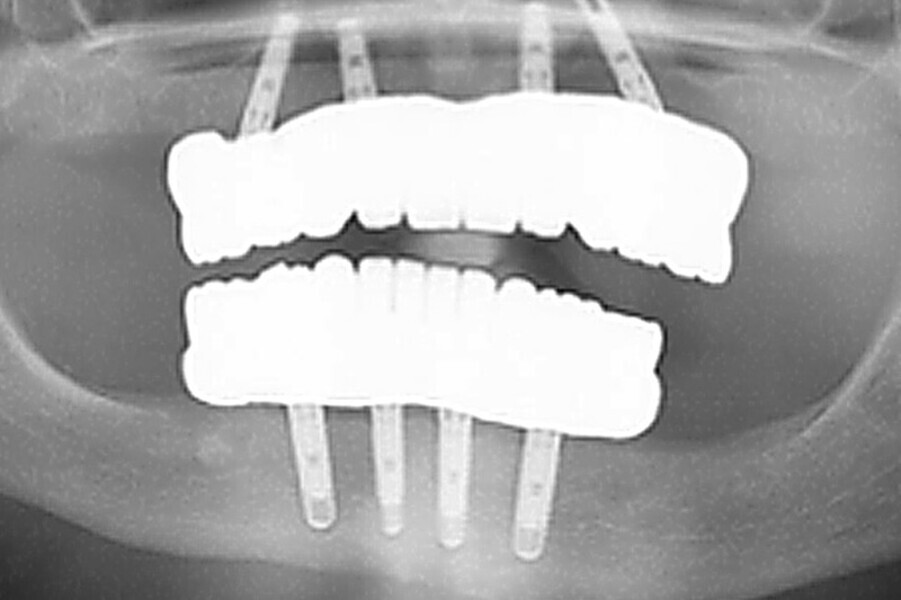

Fig. 4 Prótesis Híbrida inmediata y radiografía control con 6 años post-operatorio

Fig. 5. Prótesis Híbrida inmediata y radiografía control con 6 años post-operatorio

Fig. 6. Prótesis Híbrida inmediata y radiografía control con 6 años post-operatorio